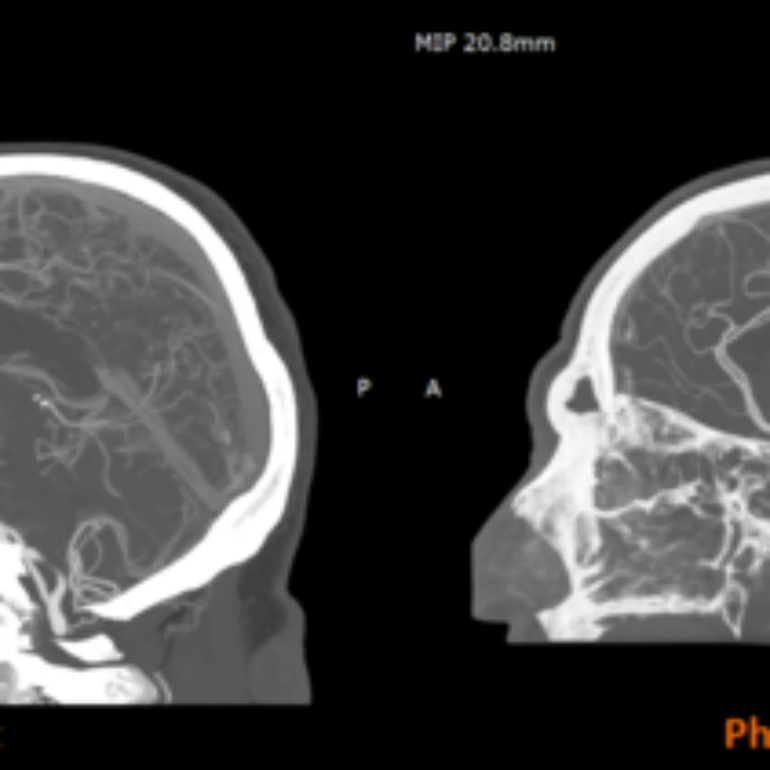

RadioMatrix: Stratasys Expands Access to Patient-Specific Radiopaque 3D Printing for Medical Imaging

3D printer OEM Stratasys has announced that its RadioMatrix radiopaque 3D printing material is now fully commercially available in the United States. Previously deployed in limited settings, the material can now be widely used by healthcare providers, medical device manufacturers, and research institutions for advanced medical imaging, education, and training purposes.